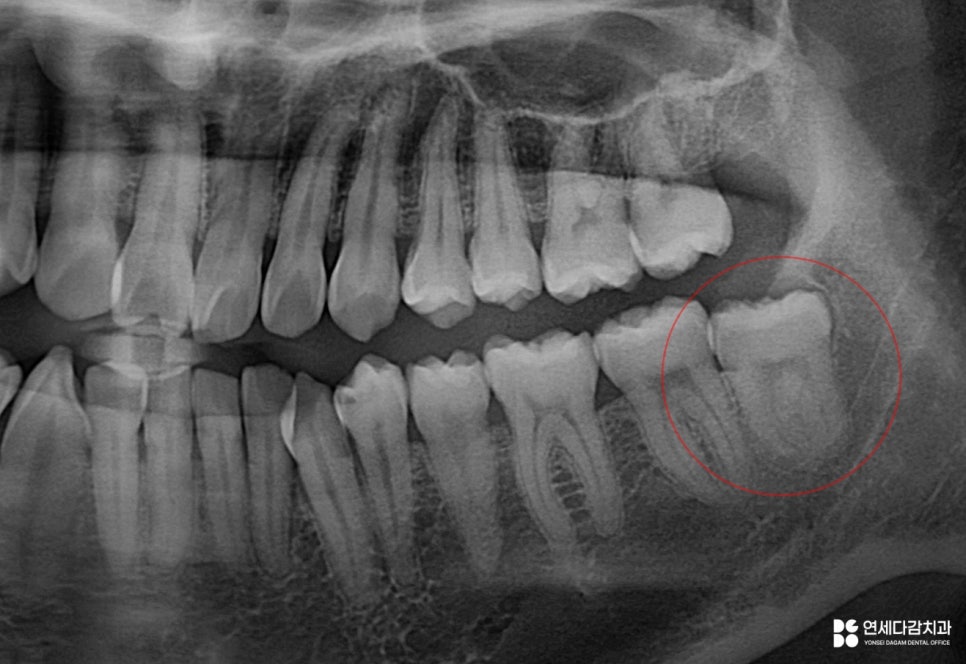

오금역 치과 에서 종합적으로 고려했을 때,

청결관리가 되지 않고 대합 되는 치아 또한 없습니다.

이는 기능적으로 이용하지 못할 뿐만 아니라,

구강 건강에 해를 끼칠 수 있으므로

발치가 건강 측면에는 유리합니다.

아래쪽 구치부에서 치아를 뽑을 때는

매우 신중한 접근이 필요합니다.

하악 부위는 중요한 신경이 지나가는 곳으로

발치 시 신경 손상을 방지하기 위한

정밀한 계획을 수립해야 됩니다.

그래서 오금역 치과 에서는

CT 분석이 중요하다고 말씀드립니다.

2025.12.14

이는 2차원적인 엑스레이와는 다르게

입체적으로 치근단과 신경관의 관계를

시각화여 보여주는 장비입니다.

주행 경로를 정확히 파악할 수 있으며,

치아 뿌리의 각도와 방향까지 정확히 보여주어

발치 시 어떻게 분리해야 될지

어떤 방식으로 접근해야 되는지에 대한

섬세한 계획을 세울 수 있습니다.

해당 케이스는 신경관이 치근 끝에 닿아 있어

최소한의 자극으로 진행해야 됩니다.

특히 원심 부위는 잇몸 속에 묻혀 있으므로

절개 후 뼈를 정리하는 과정이 필요합니다.